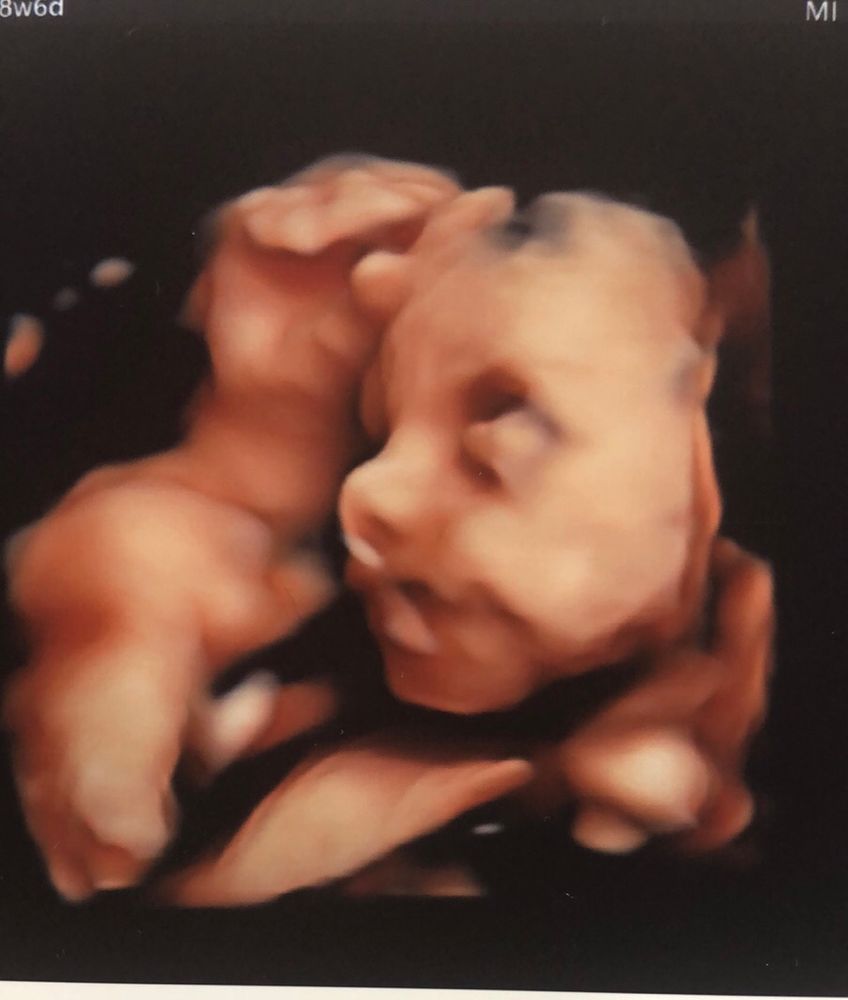

В ожидании чудаВремя летит очень -очень быстро, не смотря на все проблемы в этот раз чувствую себя легко и хорошо. Вчера посетила плановый приём у врача впервые после госпитализации. Прибавка составляет уже практически 10 кг, ож-88 см. По узи малыш активный , веч поставили - 1350 . Если раньше опережал по бпр на неделю-две , теперь отстаёт уже по параметрам на неделю . Зато по длине бёдра опережает на неделю, а по окружности животика так уже на целых две. Ну что же, дети растут не равномерно . У него вроде все хорошо. Сделали фото 4д узи , такой большеносый милаш. Больше похож на европейца, чем на азиата .